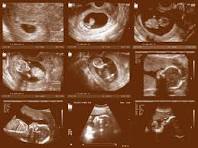

But I was rather astounded to recently learn that some pro-abortion bioethicists now deploy the obscure philosophical field of “mereology” — which explores the relationship between parts and wholes — to argue unscientifically that the gestating baby is actually merely a “part” of the woman’s body:

Recently, Kingma has argued that, contrary to popular belief, the fetus is not merely contained by the gestator’s body but a part of it. This is a metaphysical claim which is grounded by scientific facts about pregnancy. [Citations omitted.]

When thinking about whether the analogy with the bun and the oven is reasonable, Kingma argues that it is actually quite preposterous: ‘We cannot take ‘the bun out of the oven’, check it and stick it back in if it is not fully cooked. (If only!) Birth is irreversible: once a baby is out, it does not go back in — ever’. Given that it fails to satisfy Smith and Brogaard’s criteria for being a separate entity, Kingma concludes that one ought to consider the fetus as a part of the gestator’s body. She calls this the Parthood View of pregnancy.

Please understand that this ongoing debate, which is mostly taking place in ivory tower obscurity, is acutely relevant to future abortion public policy. Indeed, if the medical and bioethics elite ever reach a consensus that a fetus is merely a body part — like, say, an appendix — and not an individual living organism, that view (follow the metaphysics!) will be incorporated into public policy obliterating the regulation of abortion in any regard whatsoever.